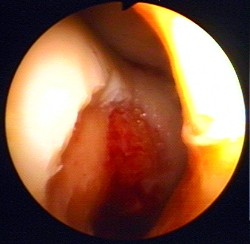

Grundsätzlich unterscheidet man vier Schweregrade des Knorpelschadens:

- Grad 1: Erweichung des Knorpels

- Grad 2: Aufrauung der Knorpeloberfläche

- Grad 3: kraterförmiger Defekt des Knorpels

- Grad 4: Fehlen der gesamten Knorpelschicht bis zum Knochen

Um das Ausmaß des vorliegenden Knorpelschadens abschätzen zu können, wird eine Magnetresonanztomographie (MRT) durchgeführt. Das exakte Schädigungsausmaß sieht der Arzt jedoch erst bei einer Gelenkspiegelung (Arthroskopie). Bei dieser minimalinvasiven Operation sollte gleichzeitig an Knorpelaufbau gedacht werden. Hierbei stehen mehrere Techniken zur Verfügung. Abgelöste Knorpelstücke sollten wenn möglich wieder fixiert, andernfalls entfernt werden. Durch Mikrofrakturierung oder Abrasionschondroplastik kann der Knorpeluntergrund angefrischt und dadurch eine Ersatzknorpelbildung angeregt werden. Wie der Name schon sagt, handelt es sich hierbei lediglich um einen Ersatz des ursprünglichen Knorpels, der diesen auch funktionell nicht vollständig ersetzen kann. Deshalb ist eine Knorpeltransplantation die bessere Wahl.

Zunächst erfolgt während eines arthroskopischen Eingriffs (Gelenkspiegelung) in unserer Gelenk-Klinik die Entnahme des körpereigenen Knorpelgewebes. Aus diesem entnommenen Gewebe werden die Knorpelzellen in einem hoch spezialisierten Zellkulturlabor isoliert und unter sterilen Bedingungen kultiviert.

Das Knorpelgewebe wird dabei aus einem gesunden, wenig belasteten Bereich des Gelenkes entnommen. Der Eingriff erfolgt ambulant und dauert ca. 30 Minuten. Gleichzeitig werden dem Patienten ca. 120–150 ml Blut entnommen. Dieses Blut benötigt das Labor zur Serumgewinnung.